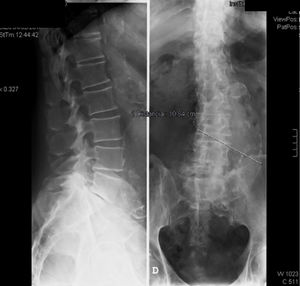

En la exploración física se objetivó en la columna vertebral: mínima escoliosis, presión lumbar negativa, limitación a la flexo-extensión en los grados finales, sin otras alteraciones, con un examen neurológico normal. En la radiología simple se objetivó escoliosis lumbar, listesis menor del 20% de L5 sobre S1, con discopatía, fenómeno de vacío y esclerosis posterior sugestiva de artrosis. La aorta abdominal se encontró calcificada, con una importante dilatación aneurismática de aproximadamente 10cm de diámetro (fig. 1).